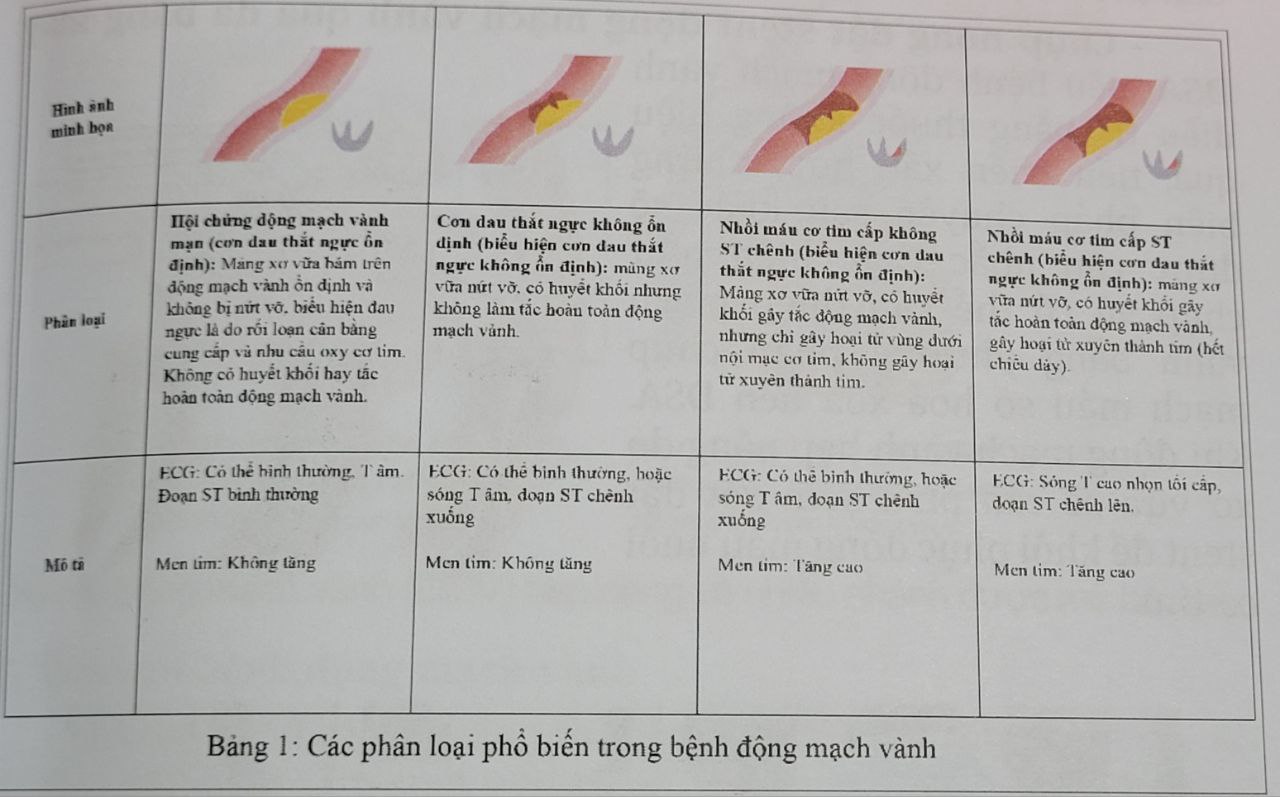

5. Các mức độ của bệnh động mạch vành

Các phân loại phổ biến trong bệnh động mạch vành

Các phân loại phổ biến trong bệnh động mạch vành